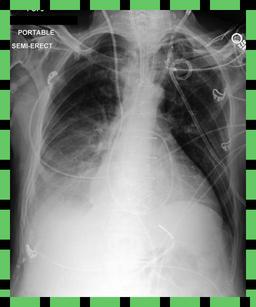

Curation of imaging datasets

CXR datasets [36] often contain multiple image acquisitions in a single visit due to data quality issues such as a limited field-of-view or scanning the wrong body part (Figure A.7). Unlike [9, 32, 81], we conduct curation to choose higher quality images among the potential candidates instead of performing a random selection. For this step, a separate BioViL-T is trained on ‘clean’ studies with single acquisitions and later used in a zero-shot setting to detect out-of-distribution samples [26, 27] arising from the re-imaging process. The candidate is selected as follows: for a margin . This approach is applied to enhance the quality of the temporal classification dataset given its limited size.

A.4 Data curation of imaging datasets

Large datasets often contain instances that are mislabelled or out of distribution [35]. We used BioViL-T to perform pairwise ranking of instances in MIMIC-CXR (Section 3.3, ) and selected representative examples found in the dataset. Our method is able to select the most appropriate image for a range of different image-acquisition or image-processing issues (Figure A.7).

We found that many lateral acquisitions in the dataset were unexpectedly labelled as frontal (Figure 7(a)). Some images contained only noise (Figure 7(b)), non-human samples (Figures 7(d) and 7(e)) or incorrect anatomy (Figure 7(g)). Often, acquisitions with an incomplete field of view (FOV) (i.e., the lungs are not completely visible) were repeated (Figure 7(c)). Lastly, post-processed images were detected by the algorithm such as contrast-enhanced scans (Figure 7(i)) that are not often used for diagnostic purposes in clinical practice.